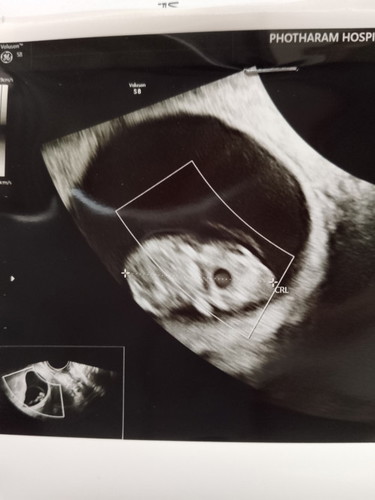

เมื่อ2อาทิตย์ที่แล้วไปซาวตอน7w3dไม่เจอน้อง แม่กังวลมากกลัวจะไม่เจอน้อง วันนี้หมอนัดไปซาวซ้ำ เจอน้องแล้วค่ะ พร้อมได้ยินเสียงหัวใจด้วย ดีใจมากๆเลยค่ะ 9w3d 😍🥰

วันนี้7w1dไปซาวเจอน้องแต่ตัวเล็กมาก มีหัวใจ หมอนัดอีก2อาทิตย์ ลุ้นยิ่งกว่าอะไรอีก😅